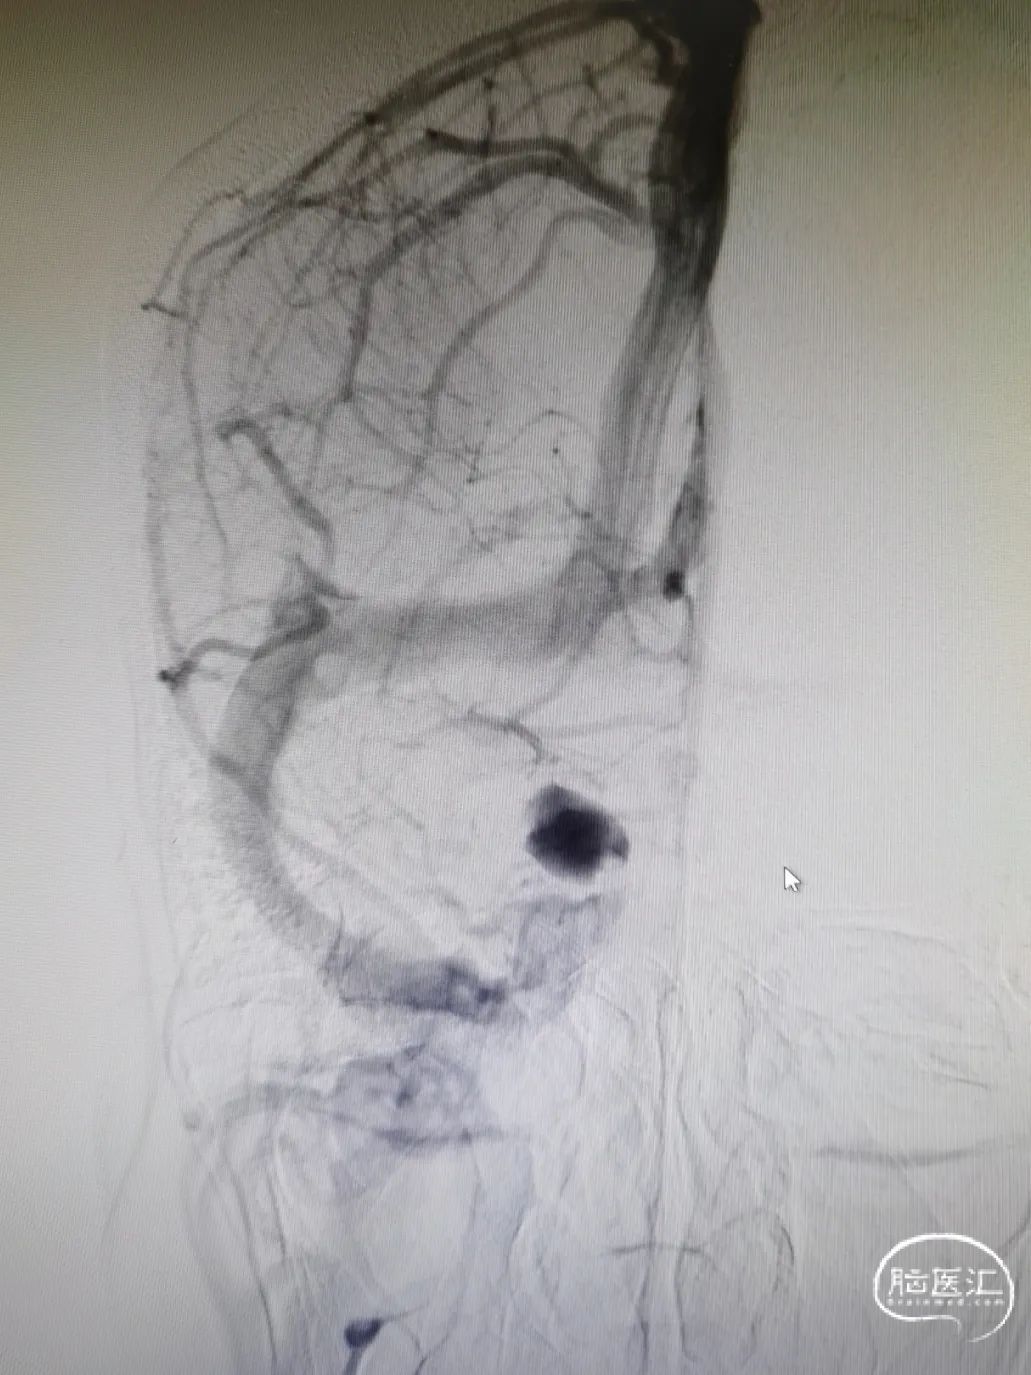

DSA造影

造影提示主动脉弓开口尚可,但颈动脉迂曲明显。

前交通囊状动脉瘤约4mm╳3mm,瘤颈约4mm。

右颈内动脉交通段以远瘤样扩张,载瘤动脉完全瘤化,局部可见多处小阜突起,无明显瘤颈,最大约16mm╳11mm。

右侧后交通动脉自瘤体远端发出。

右侧大脑中动脉直径约3mm,颈内动脉海绵窦段约4.5mm。

图4